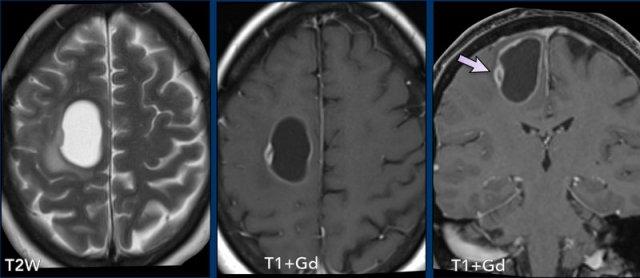

Đây là hình ảnh của bệnh nhân nam 55 tuổi với triệu chứng đau đầu.

Hãy quan sát hình ảnh trước rồi tiếp tục đọc.

Câu hỏi:

- Chẩn đoán có khả năng nhất là gì?

- Những dấu hiệu nào là điển hình cho chẩn đoán này?

Các dấu hiệu bao gồm:

- Có hai tổn thương ngấm thuốc dạng vòng được bao quanh bởi phù não

- Trên chuỗi xung T2W, dấu hiệu viền đôi (double rim sign) hiện diện ở tổn thương thùy trán trái.

- Có hạn chế khuếch tán ở trung tâm.

- Có ngấm thuốc viền nhẵn.

Tất cả các dấu hiệu này phù hợp với chẩn đoán áp-xe não.

Dấu hiệu viền đôi trên chuỗi xung T2W có thể gặp trong tới 75% các trường hợp.

Điển hình là có ngấm thuốc viền hoàn toàn và hạn chế khuếch tán, nhưng đôi khi ngấm thuốc không hoàn toàn do ổ áp-xe hướng về phía não thất, chuẩn bị đổ mủ vào hệ thống não thất.

Có thể thấy sự khởi đầu của quá trình này ở ổ áp-xe thùy trán phải.

Khi ổ áp-xe này vỡ vào não thất, viền ngấm thuốc sẽ bị gián đoạn và sẽ xuất hiện hạn chế khuếch tán trong lòng não thất.